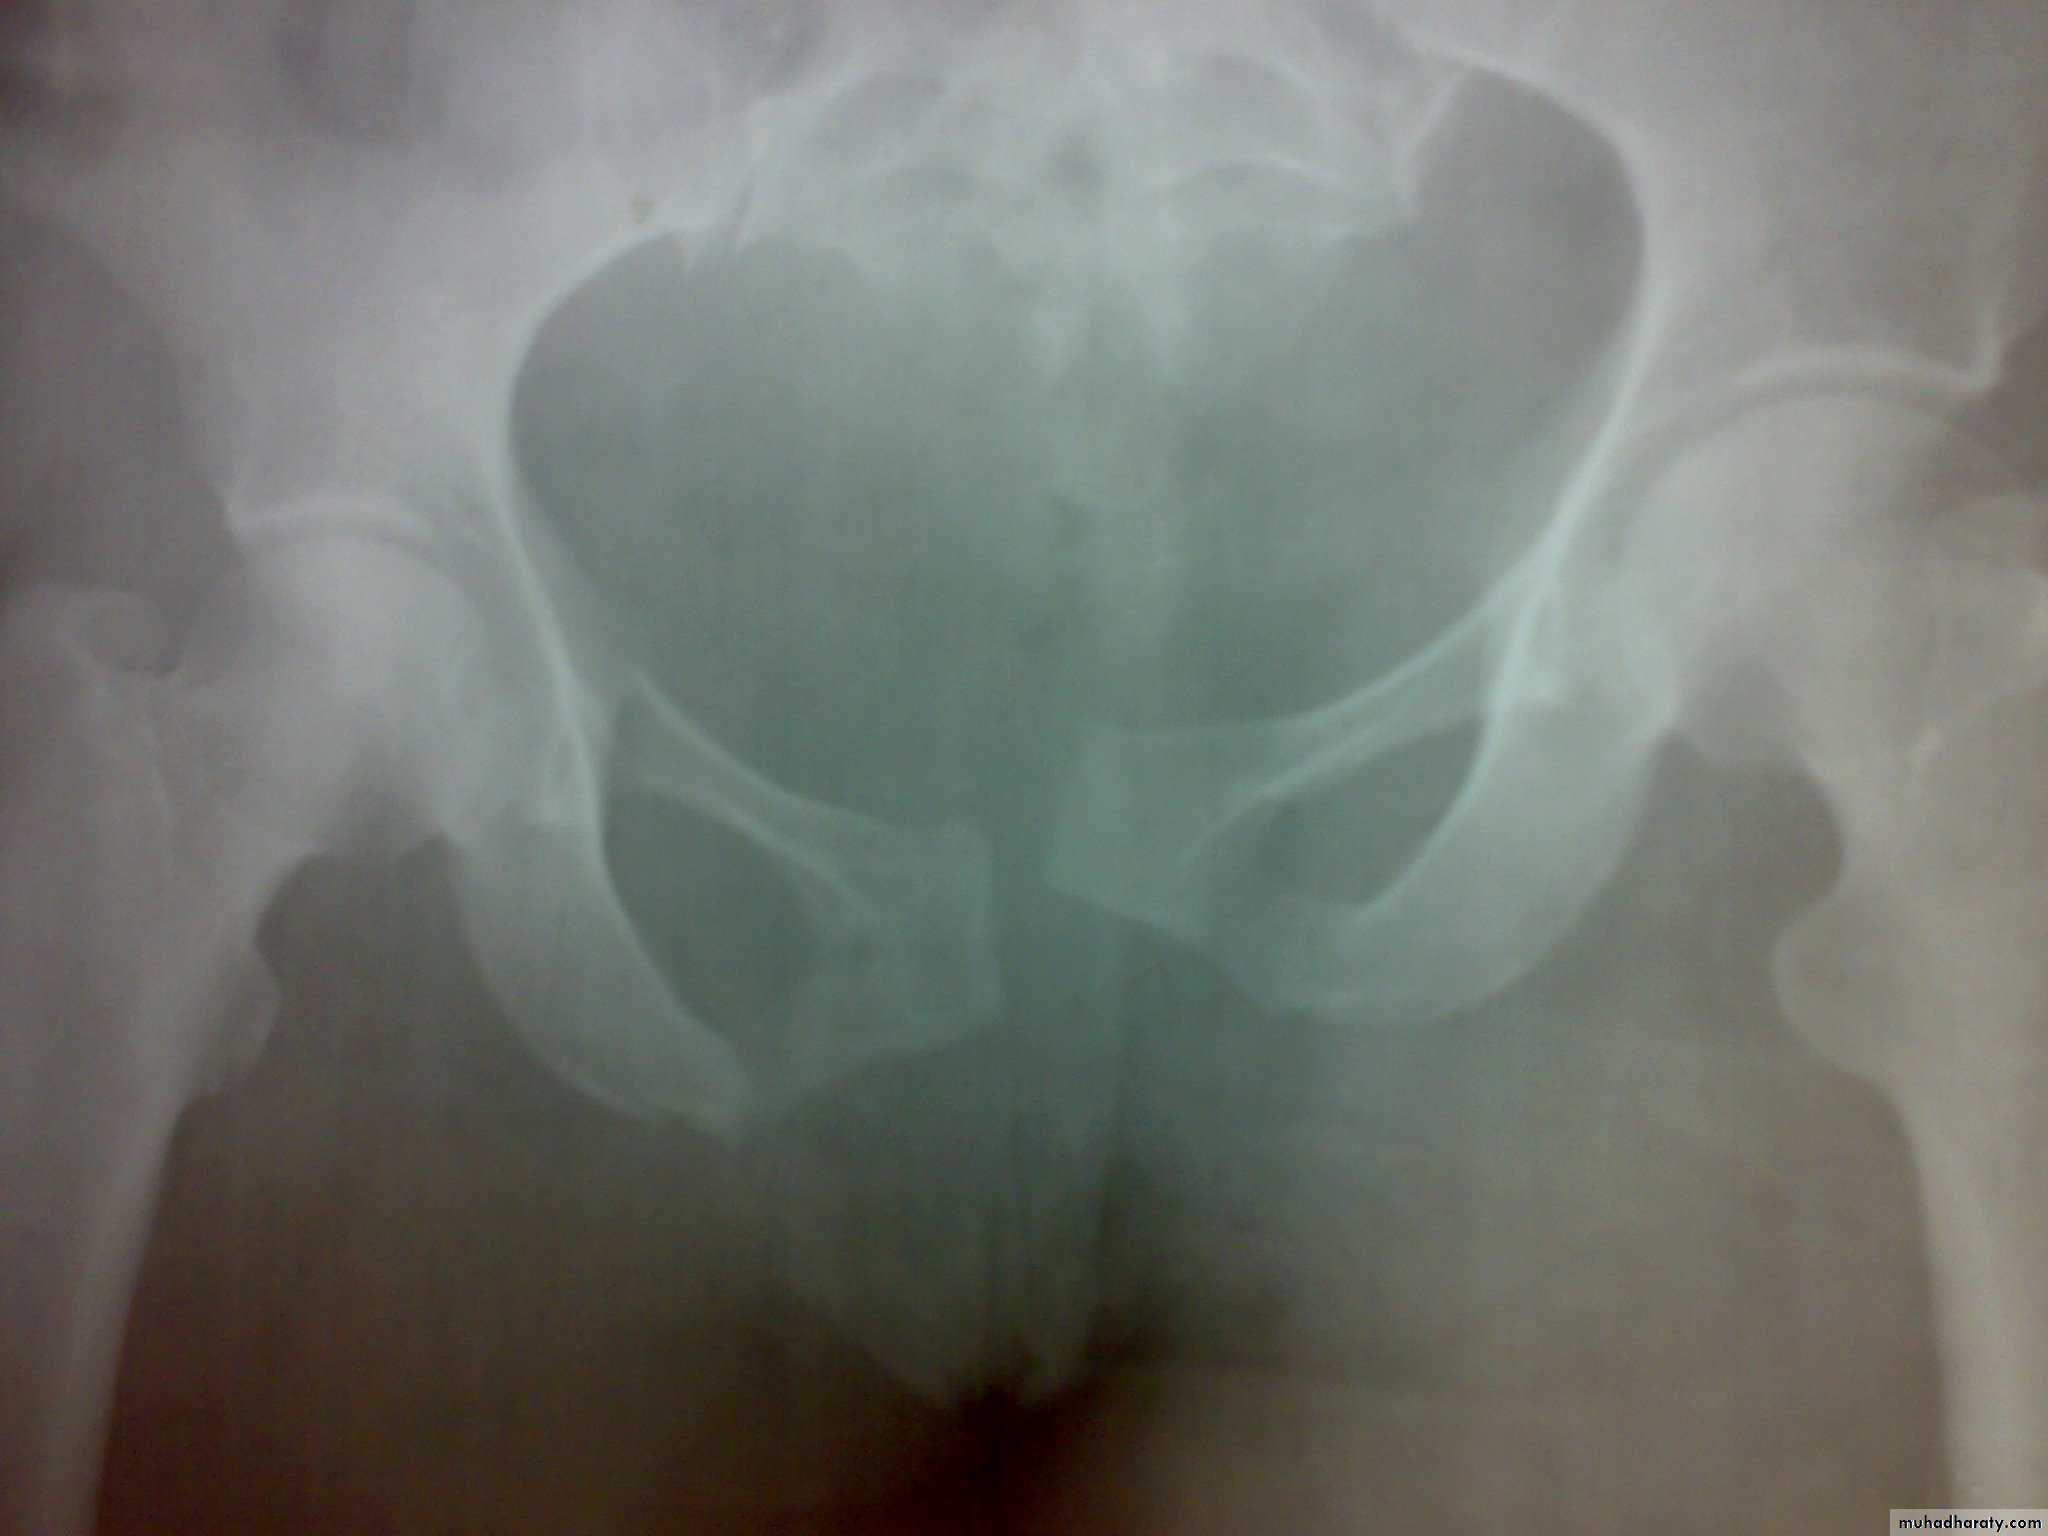

Unstable ring fractures

Caused by sever trauma.Extremely serious.

Carries high risk of visceral injuries.

There are fractures around or separation of symphysis pubis or sacroiliac joint.

Severe bleeding is the main cause of death following high-energy pelvic fractures. If there is an unstable fracture of the pelvis, hemorrhage will be reduced by rapidly applying a pelvic binder or an external fixator.

Treatment of the fracture

Open book injuries with a gap of less than 2cm at the symphisis pubis can be treated with bed rest for 6 weeks. If the gap is more than 2cm, external fixator with pins in the iliac blades and anterior bar may be used for 8-12 weeks. The other option is anterior plating.Severe vertical shear and compression injuries are the most dangerous and most difficult to treat. The fracture or dislocation must be stabilized by external fixation or posterior iliosacral screw or anterior plating with posterior iliosacral screw . Vertical force fractures may be treated by open reduction and internal fixation or skeletal traction and non weight bearing for 3 months